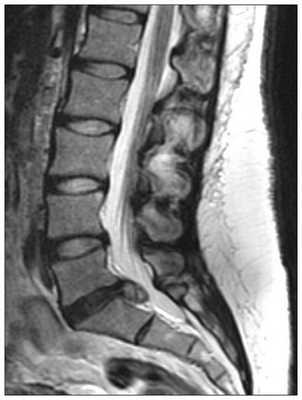

МРТ поясничного отдела позвоночника. Т2-взвешенная сагиттальная МРТ. Стеноз позвоночного канала.

Оценка состояния поясничного отдела позвоночника после операции составляет важную и сложную задачу. МРТ СПб позволяет выбирать место обследования после операции. От правильной трактовки выявленных изменений зависит выбор дальнейшей тактики лечения пациента. Современный взгляд на проблему может быть назван «междисциплинарным», так как требует кооперации специалистов разного профиля: спинальных хирургов (нейрохирургов), лучевых диагностов, специалистов-реабилитологов (физиотерапевтов и т.д.).

Дифференциальная диагностика между фиброзом и рецидивной грыжей является ключевым моментом для выбора тактики лечения. Интенсивность сигнала на неконтрастированных МРТ позвоночника у них одинаковая. Грыжа является продолжением диска, и она обычно отграничивается гипоинтенсивной задней продольной связкой. Однако при секвестрации эта связь теряется и подобно фиброзу секвестр может располагаться в стороне от диска. Ретракция дурального мешка в сторону образования косвенно указывает на фиброз, компрессия дурального мешка характернее для грыжи. Эти признаки имеют очень невысокую степень специфичности. Диск и грыжа образования бессосудистые, грануляционная ткань и фиброз, напротив, содержат сосуды. Поэтому при МРТ они контрастируются, что позволяет отличать рубец от рецидивной грыжи. Контрастирование связано с наличием васкуляризации. Точность метода МРТ превышает 90%. Проблема состоит в том, что рецидивная грыжа и эпидуральный фиброз не исключают друг друга, а часто сосуществуют. Это существенно затрудняет постановку правильного МРТ диагноза.

МРТ поясничного отдела позвоночника. Рецидивная грыжа диска. Т2-зависимые МРТ в сагиттальной и аксиальной плоскостях.